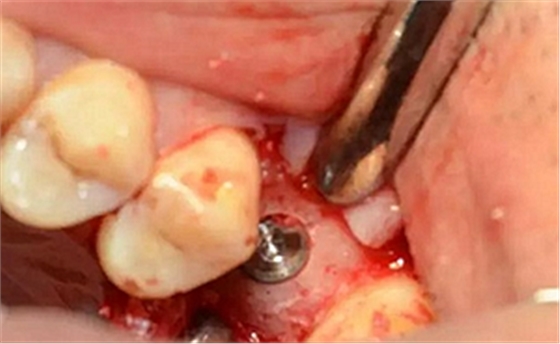

植入種植體,注意方向控制和初期穩(wěn)定性。

上覆蓋螺絲